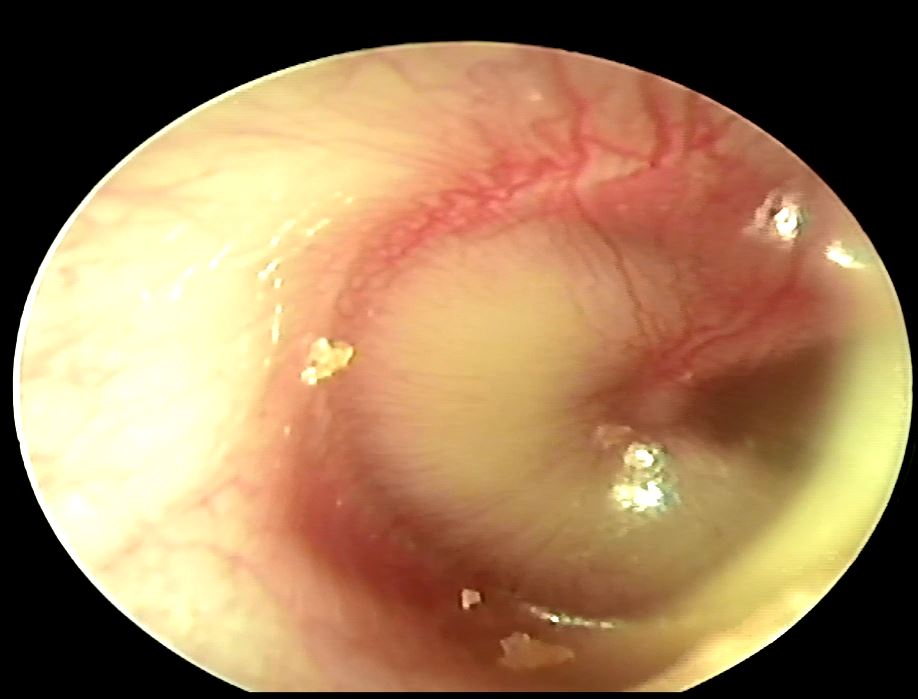

中耳腔藉由耳咽管平衡裡面的壓力,如果耳咽管本身阻塞或是呼吸道的纖毛運動變差,原本裡面的黏液就排不出來,久了就會形成積水狀,積水一多就有可能會造成耳鳴、耳悶、聽力減退等等現象;中耳腔積水又稱為glue ear,意思就是裡面可能會有清澈的或是黏稠的液體,孩子一般會有輕度聽力減退 (大約會掉27分貝) 或是語言發展遲滯等現象,跟急性中耳炎不一樣的地方是一般不會有耳痛、發燒或是倦怠等症狀。

中耳腔積水占所有小孩的中耳炎的25-35%,中耳腔積水一般好發在4歲以前的兒童身上,跟本身耳咽管還沒發育完全有關,超過6歲就比較少發生,美國跟歐洲的研究顯示大約有5成到8成的小孩四歲前曾經發生過中耳積水,危險因子有 : 六歲以下、在托育中心待過、很多兄弟姊妹、常常感冒、瓶餵牛奶以及家裡有人抽菸,積水的話可能以後比較容易出現耳膜穿孔、鼓室硬化症、耳漏、膽脂瘤等等問題;積水的話不見得會發燒也不見得積水裡面就會有細菌滋生,所以抗生素的使用其實在醫界是有爭議的,至於抗組織胺、去充血劑以及鼻內類固醇也是沒有一個定論。